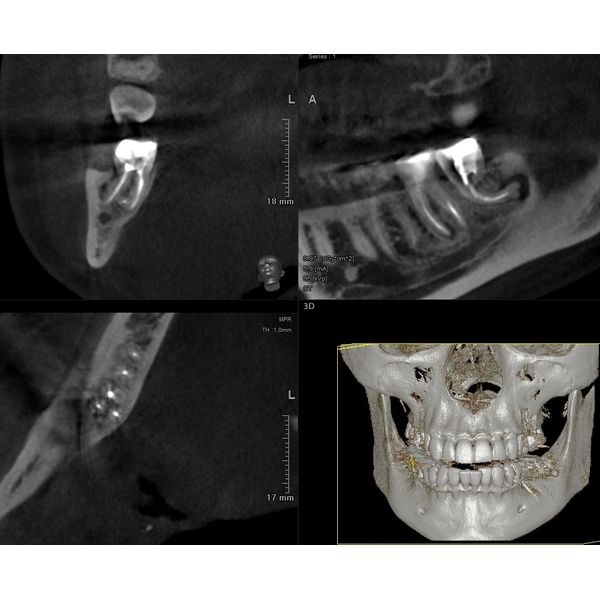

По результатам конусно-лучевой компьютерной томографии (КЛКТ) от 23.10.2022 года, в корневых каналах зуба 4.8 выявили следы пломбировочного материала, не доходящего до верхушки корня. В этой области отмечался овальный очаг разрежения кости с отчётливыми границами размером около 0,5 см в поперечнике.